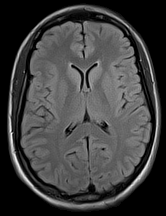

3.2.2 Example 1: Scan acceleration

The used data is obtained from the publicly available fastMRI brain dataset (citep \@BBN(Zbontar et al., 2019)), which consists in total of 640564056405 T1, T2 and FLAIR 3D k-space volumes. The fastMRI challenge series provided MRI datasets to foster the development of accelerated reconstruction algorithms. The series consists of a knee MRI dataset and challenge in 2019 (citep \@BBN(Knoll et al., 2020)), of a brain dataset and challenge in 2020 (citep \@BBN(Muckley et al., 2021b)), and of a prostate dataset in 2023 (citep \@BBN(Tibrewala et al., 2023)). The winners of the challenges were selected by the comparison of the provided reference images, created by the rSOS of the fully sampled data, to the image outputs of the proposed method via the SSIM and the highest ranked results were submitted to receive experts’ opinion.

We show here images obtained from two machine learning reconstruction algorithms that took part in the fastMRI multi-coil brain dataset challenge in 2020, namely the end-to-end variational network E2E-VarNet (citep \@BBN(Sriram et al., 2020)) and XPDNet (citep \@BBN(Ramzi et al., 2021)). XPDNet was among the top three submissions of the challenge and both algorithms perform very well on the corresponding public leaderboard (citep \@BBN(Facebook AI, )), that allows comparison of algorithms submitted after the challenge deadline. The authors of the XPDNet Algorithm provided two distinct models for the acceleration factors, we employ the neural network provided for acceleration factor 4.

The reconstructions in Figure 5 were obtained by the application of E2E-VarNet, Figure 5 (b)(c)(e)(f), and XPDNet, Figure 5 (a)(d), to accelerated data with random masks (acceleration factor between 1 to 5) in the frequency domain.

Refer to caption

(a) (27.8, 0.78, 0.14)

(b) (29.6, 0.85, 0.14)

(c) (32.3, 0.92, 0.04)

(d) (29.5, 0.84, 0.12)

(e) (29.6, 0.86, 0.12)

(f) (33.0, 0.94, 0.04)

Figure 5: Reconstruction outputs of accelerated FLAIR MRI data from the algorithms Xpdnet(a)(d) and E2varnet (b)(c)(e)(f). The bottom images (d)-(f) are judged by PSNR/SSIM/LPIPS as better reconstructions than the respective image above them (a)-(c), although visually they clearly have worse quality.

FR-IQA mismatch

We can see in Figure 5 that the visual quality of the obtained images does not correspond to the numbers provided by PSNR/SSIM/LPIPS. This is not surprising as some challenges with SSIM as a performance metric have already been discussed in the official results paper of the challenge (citep \@BBN(Muckley et al., 2021a)) and small artefacts/wrong lesions have been shown. Here, we complement with examples where the visual results clearly ask for a different judgement even in a non local manner. In particular, the bottom images in Figure 5 show stronger artefacts and loss of information in comparison to the images on top. In addition, the degraded images (e) (f) do hold quite higher numbers in comparison to (a) which is nearly noise-free.